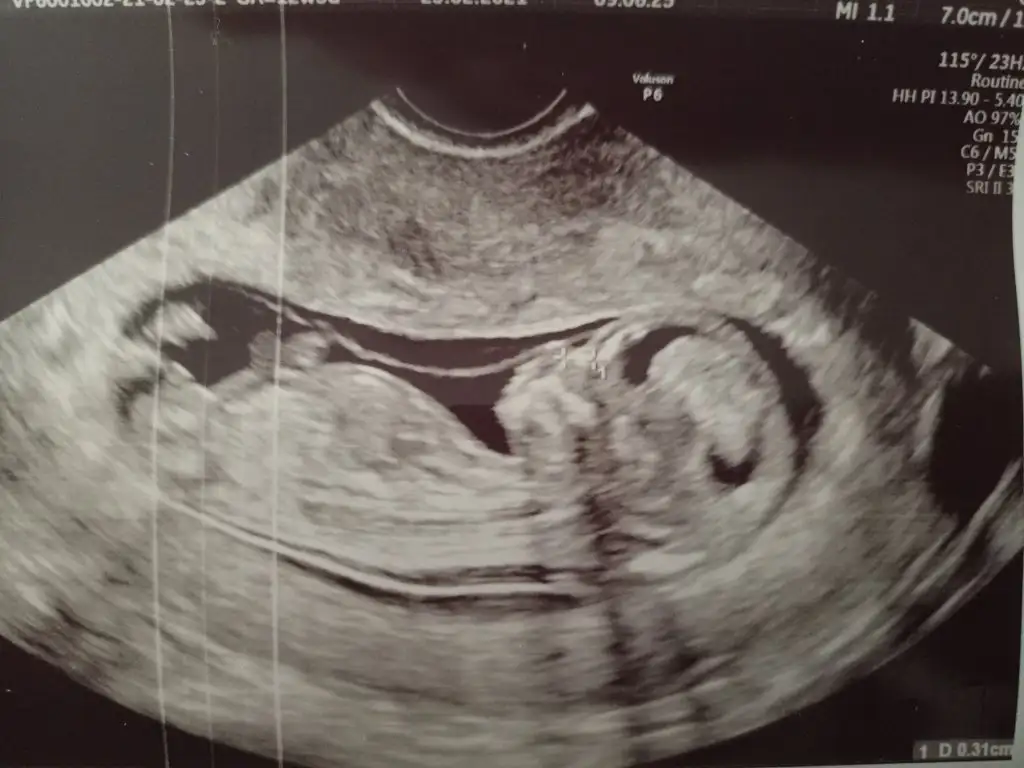

Kızlar Merhaba, bugün 12+5 ve ikili tarama için ultrason yapıldı. CRL 6.6 haftası ile uyumluymuş ancak ense kalınlığı 2.3 çıktı. Doktorum sınırın 2.5 olduğunu ve sınıra yakın olduğu için Down Sendromu riski içerdiğini söyledi. Nipt önerdi ancak bunun için kan tahlilinin de sonucunu bekliyorum. 26 yaşıma yeni girdim, hep sağlıklı beslenirim, alkol ve sigara kullanmıyorum. Yani risk grubunda değilim bu yüzden telaşlıda değilim ama yine de moralim bozuldu. Benzeri bir durum ile karşılaşan oldu mu?